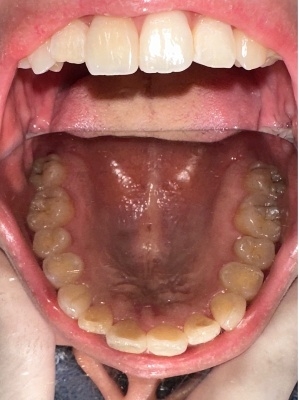

上顎